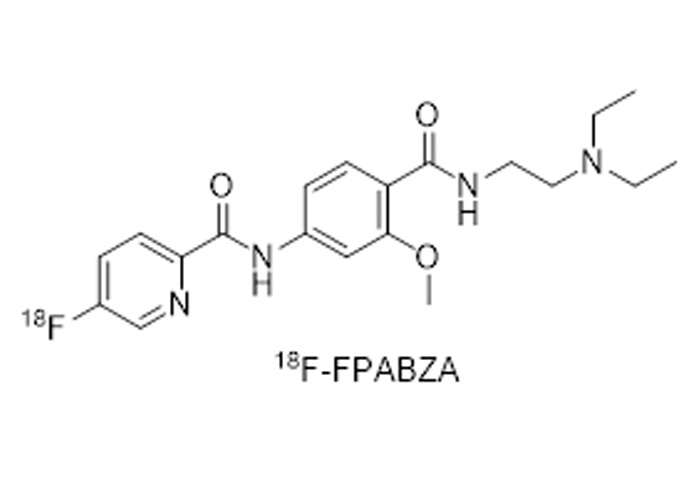

對(duì)18F、11C、68Ga、等核素示蹤劑的(de)合成與國(guó)外(wài)主流示蹤劑合成平台達到(dào)同一(yī)水(shuǐ)<平;

公司的(de)核心産品有(yǒu)先進的(de)放(fàng)射性藥物(wù)自(zì)動合成系統的(de)設計(jì)和(hé•)制(zhì)造,以及PET示蹤劑的(de)設計(jì)、合成及生(shēng)産。